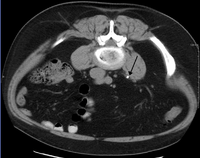

Otherwise a noncontrast helical CT scan with 5 millimeters (0.2 in) sections is the diagnostic modality of choice in the radiographic evaluation of suspected nephrolithiasis.[12][42][45][46][3] All stones are detectable on CT scans except very rare stones composed of certain drug residues in the urine,[47] such as from indinavir. Calcium-containing stones are relatively radiodense, and they can often be detected by a traditional radiograph of the abdomen that includes the kidneys, ureters, and bladder (KUB film).[47] Some 60% of all renal stones are radiopaque.[45][48] In general, calcium phosphate stones have the greatest density, followed by calcium oxalate and magnesium ammonium phosphate stones. Cystine calculi are only faintly radiodense, while uric acid stones are usually entirely radiolucent.[49]

Ultrasound imaging of the kidneys can sometimes be useful, as it gives details about the presence of hydronephrosis, suggesting the stone is blocking the outflow of urine.[47] Radiolucent stones, which do not appear on KUB, may show up on ultrasound imaging studies. Other advantages of renal ultrasonography include its low cost and absence of radiation exposure. Ultrasound imaging is useful for detecting stones in situations where X-rays or CT scans are discouraged, such as in children or pregnant women.[50] Despite these advantages, renal ultrasonography in 2009 was not considered a substitute for noncontrast helical CT scan in the initial diagnostic evaluation of urolithiasis.[46] The main reason for this is that compared with CT, renal ultrasonography more often fails to detect small stones (especially ureteral stones), as well as other serious disorders that could be causing the symptoms.[10] A 2014 study confirmed that ultrasonography rather than CT as an initial diagnostic test results in less radiation exposure and did not find any significant complications.[51]